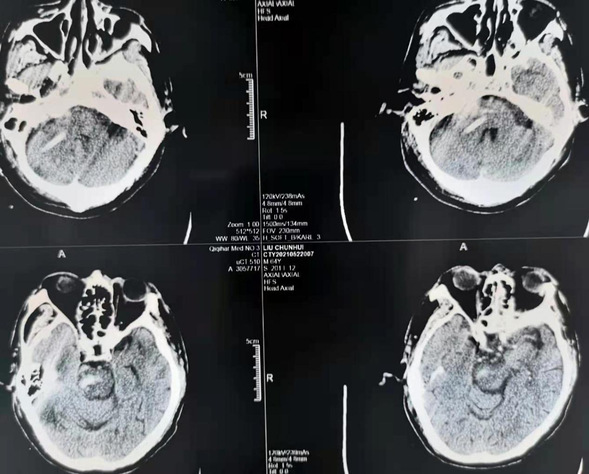

患者柳某,男性,64岁。5月20日晚突发意识障碍,送至我院,经头部CT后诊断为脑干出血。经神经外二科医疗团队讨论后决定行神经外科机器人辅助下脑干出血穿刺引流。在神经外科手术机器人的辅助下,将引流管经患者右侧小脑精准植入脑干血肿腔,手术圆满成功。

术后复查头CT